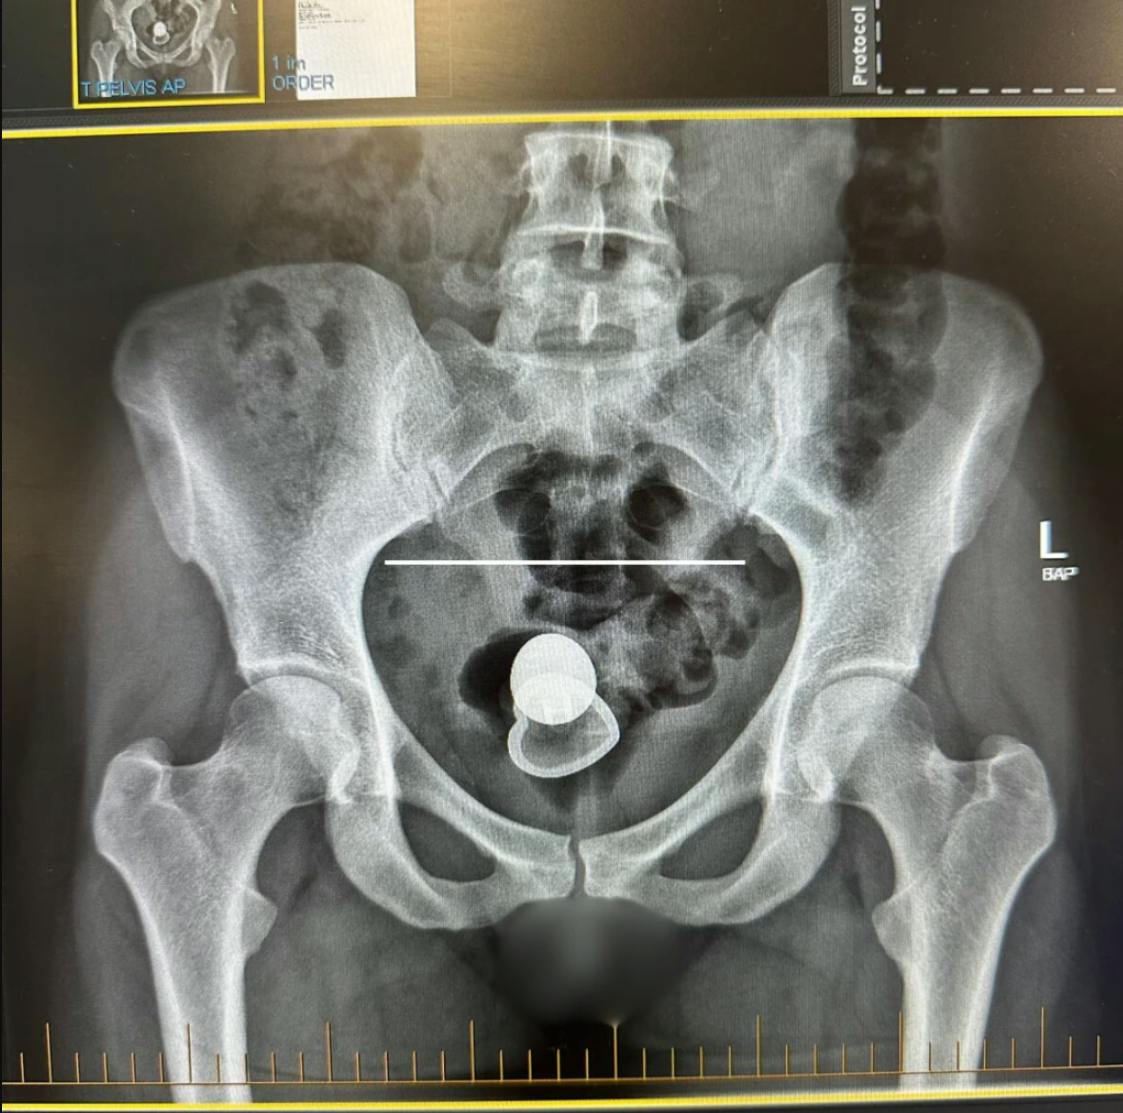

Hun troede kortvarigt, at sexlegetøjet var faldet ud af hende. Men mystisk nok var legetøjet ingen steder at se. Og så gik sandheden op for Alicia og hendes nye fyr: Legetøjet var forsvundet et sted oppe i hende.

Herefter gik turen altså mod det lokale hospital, hvor lægerne rigtig nok kunne konstatere, at sexlegetøjet havde forvildet sig så langt op, at det nok ikke ville komme retur med egen fri vilje.

- På hospitalet forsøgte to at få det ud, men de kunne ikke, fortæller Alicia i detaljer på sin TikTok.

Herefter måtte hun under kniven – men først efter to dages lang ventetid.

Lægerne lykkedes med at få sexlegetøjet ud via indgrebet. De spurgte efterfølgende, om hun ville have det med hjem.